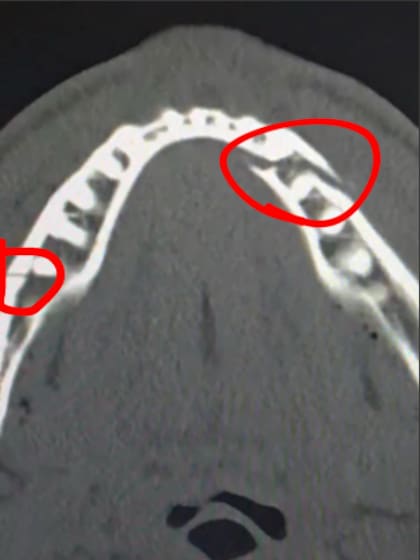

El creador de contenido devenido en boxeador, Jake Paul, fue derrotado por nocaut en el sexto asalto en su pelea ante el excampeón unificado de peso pesado Anthony Joshua, el viernes 19 de diciembre en el Kaseya Center de Miami, Florida. En su cuenta de Instagram, el influencer compartió una imagen de su doble fractura de mandíbula y un mensaje dirigido a otro campeón del pugilismo, el mexicano Saúl Canelo Álvarez.

“Doble mandíbula rota, dame a Canelo en 10 días”, fue la broma que hizo Jake Paul tras publicar una imagen en su cuenta de Instagram en la que muestra las fracturas que sufrió durante su pelea con Joshua.